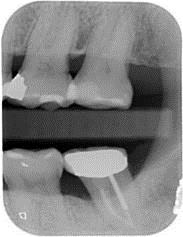

牙周初診時患者之口內觀。口內明顯牙菌斑及牙結石堆積。全口嚴重牙齦紅腫。治療前X光片。#37的近心側有較深的骨內缺損,剩餘齒槽骨高度只有20%。